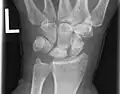

Left hand x-ray post proximal row carpectomy